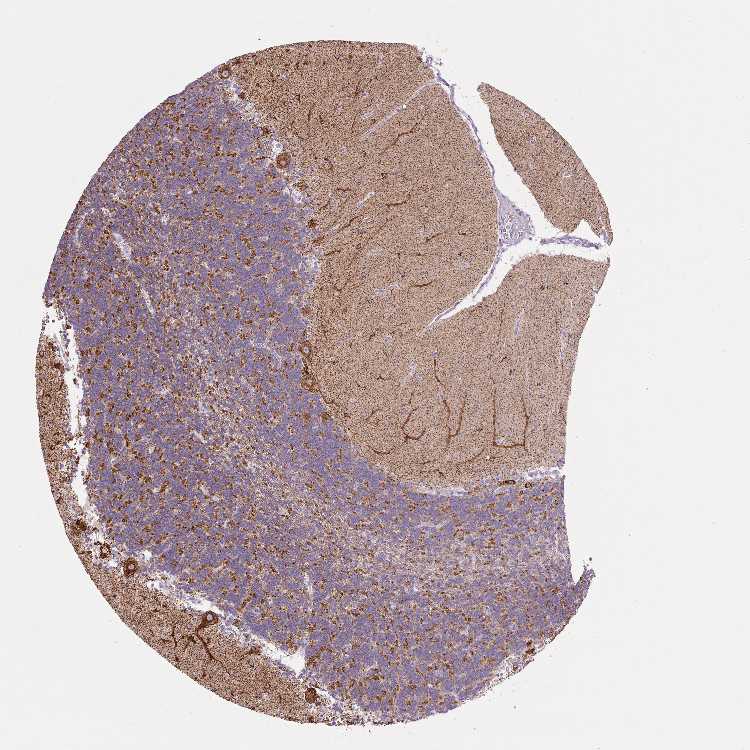

BRAIN CEREBELLUM Show tissue menu

CEREBELLUM - Expression summary

CEREBELLUM - Antibody stainingi

Antibody staining in the annotated cell types in the current human tissue is reported as not detected, low, medium, or high, based on conventional immunohistochemistry profiling in selected tissues. This score is based on the combination of the staining intensity and fraction of stained cells.

Each image is clickable and will lead to virtual microscopy that enables deeper exploration of all samples and also displays staining intensity scores, fraction scores and subcellular localization as well as patient and tissue information for each sample.

Antibody HPA052497

Purkinje cells High

Cells in granular layer High

Cells in molecular layer High